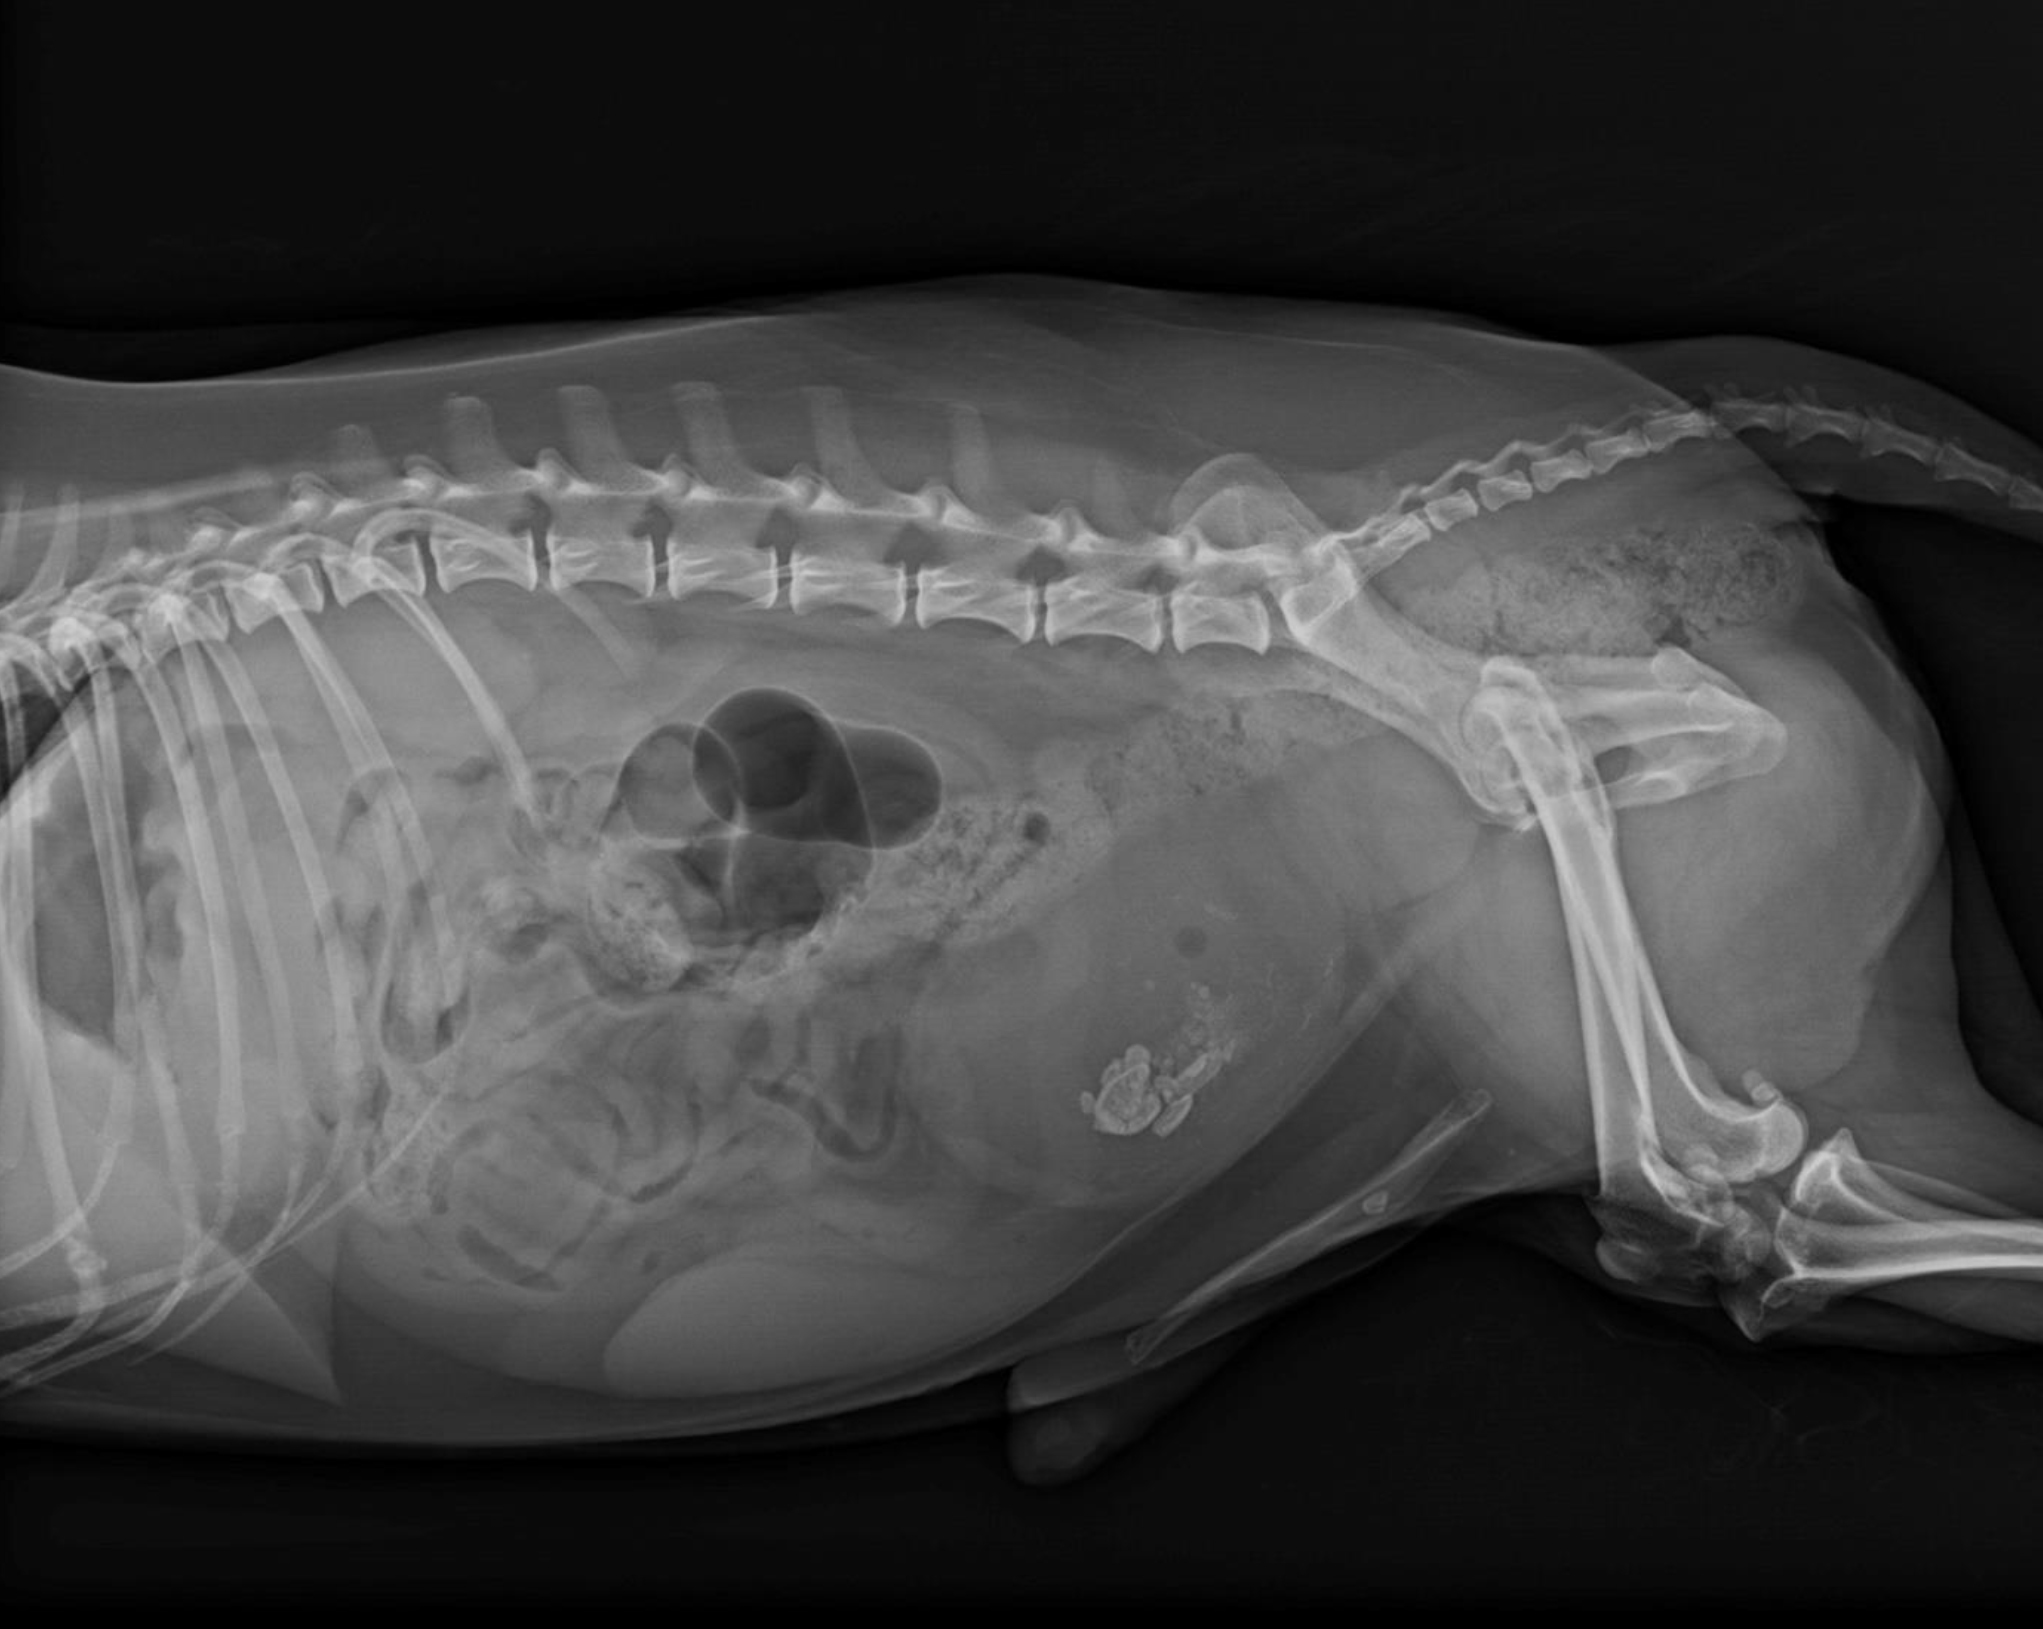

Ein anderer Fall ist der eines neun Jahre alten Kooikerrüden, der bereits mit Antibiotika anbehandelt war und wenig bis keinen Urin absetzen konnte. Der Rüde war seit zwei Jahren kastriert. Röntgenologisch zeigten sich eine stark gefüllte Harnblase und eine röntgendichte prominente Vorsteherdrüse (Prostata). Sonographisch stellte sich diese inhomogen, mit einer teilweisen Ansammlung von Calciumsalzen (kalzifiziert) dar. Im Bereich der Prostata schien eine blumenkohlartige Wucherung in der Harnröhre vorzuliegen, die den Urinabsatz blockierte.